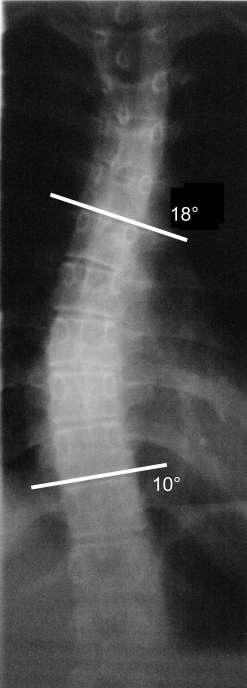

Wenn ich das Röntgenbild richtig vermessen habe (siehe Anlage), sind die Winkel thorakal 18° und lumbal 10°. Ich denke, dass man damit durchaus Rückenpatientin ist. Wir haben deshalb einen neuen Termin beim Orthopäden Dr. Balik in Hamm vereinbart, um dessen Meinung zu hören.

Hallo, das sind mehr Grade, als die, die du ausgerechnet hast. Ich würde sagen oben und unten jeweils ca. 25°. Aber zu eurem Glück hat deine Tochter noch sehr wenig Rotation, die Betonung liegt aber auf noch! Deine Tochter hat unbehandelt durchaus Potential auf >40° abzurutschen, also MACH etwas.

Es handelt sich hierbei nicht um 2 Winkel, man muß zur Bestimmung des Winkels beide (oben und unten) addieren. Ich habe es mal grob am Bildschirm nachgemessen. Ihre Messung stimmt, es wären demnach nach Cobb 28°. Bei einer 14 jährigen besteht da unbedingt Handlungsbedarf, bestehend aus ambulanter Schroththerapie, Reha und Korsett.